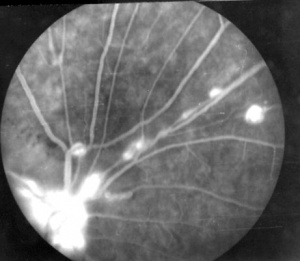

Macroaneurysms are a sine qua non condition to diagnosis of IRVAN syndrome[9]. The retinal arterioles have multiple aneurysmal dilatations extending through the first several orders of arterial branching until mid-periphery. The aneurysms are commonly found on the optic nerve, a site where typical senile retinal macroaneurysms are not. The aneurysms are typically found at branching points of the arteries, and may be fusiform, Y-shaped, or spheroid in shape. In segments between the aneurysms the retinal arteries frequently show marked caliber variations. Arterial aneurysms clinically resemble multiple and consecutive "knots of a cord" ( Figure 2 )

Fluorescein angiography highlights the arteriolar abnormalities. The aneurysms are more evident and the alterations in arteriolar caliber are more obvious. Leakage of fluorescein from the aneurysms is apparent. Patients with IRVAN usually have optic nerve head staining. Of course, disc and/or retinal neovascularization show marked fluorescein leakage. The areas of peripheral non- perfusion are easier to appreciate with fluorescein angiography, especially wide-field fluorescein angiography.[23][24]